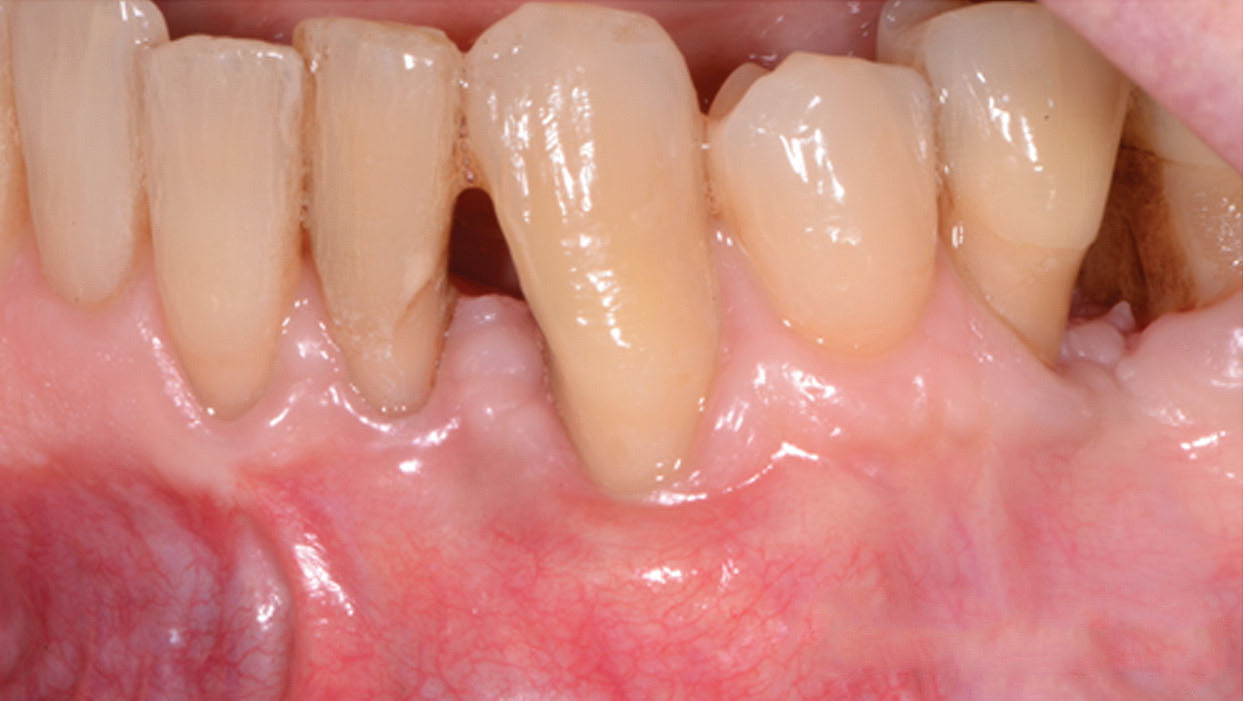

Fig 3. A 3D printed scaffold was designed using CAD software to fit a peri-osseous defect in a human patient. The scaffold consisted of a region with channels designed to support oriented PDL tissue formation and a region for the regeneration of osseous tissue. Fig 3: baseline;

Fig 4: defect model; Fig 5 through Fig 7: internal, tilted, and side views of scaffold, respectively; Fig 8 through Fig 10: coronal, middle, and apical

angles, respectively; Fig 11: cross-section diagram; Fig 12: labial scan image. (Images reprinted with permission from Rasperini G, Pilipchuk SP, Flanagan CL, et al. J Dent Res. 2015;94[9 suppl]:153S-157S.)

Fig 13. The scaffold was placed in the defect, where it remained for approximately 1 year. Fig 13: baseline; Fig 14: defect; Fig 15: scaffold matrix; Fig 16: scaffold placement; Fig 17: wound closure; Fig 18 through Fig 20: 2-month, 6-month, and 1-year postoperative, respectively. (Images reprinted with permission from Rasperini G, Pilipchuk SP, Flanagan CL, et al. J Dent Res. 2015;94[9 suppl]:153S-157S.)

Figure 13

Fig 14. The scaffold was placed in the defect, where it remained for approximately 1 year. Fig 13: baseline; Fig 14: defect; Fig 15: scaffold matrix; Fig 16: scaffold placement; Fig 17: wound closure; Fig 18 through Fig 20: 2-month, 6-month, and 1-year postoperative, respectively. (Images reprinted with permission from Rasperini G, Pilipchuk SP, Flanagan CL, et al. J Dent Res. 2015;94[9 suppl]:153S-157S.)